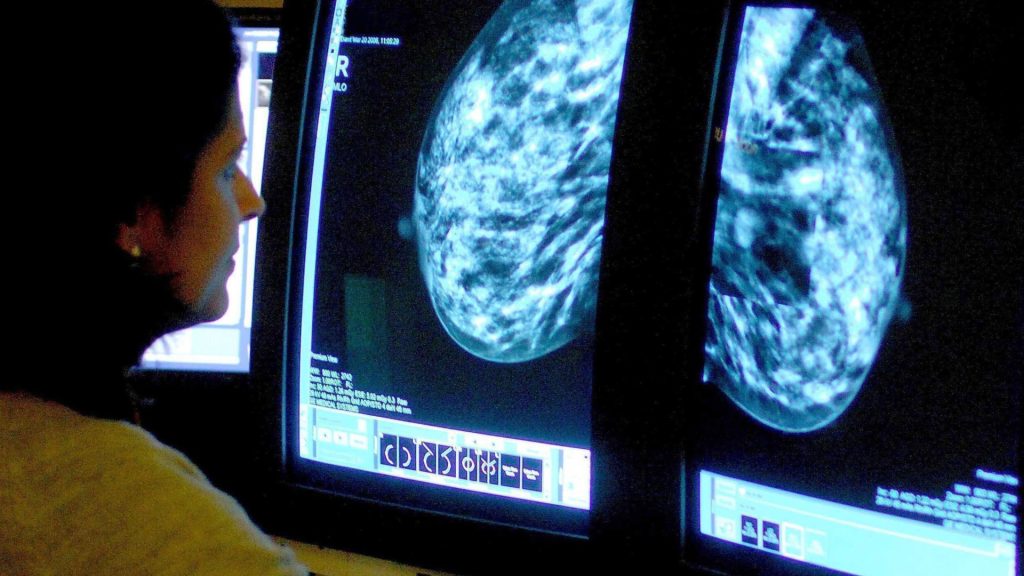

Around 56,000 women are diagnosed with breast cancer every year and it spreads – known as secondary cancer – in up to a third of cases.

Enhertu, known as trastuzumab deruxtecan, targets a specific type of cancer called HER2-low.